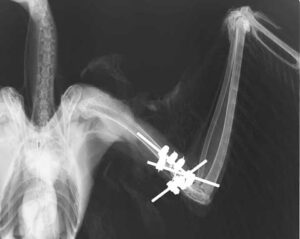

手術で整復

状態が少し安定してきたため、骨折の整復手術を行うことになりました。関節に近いところでの骨折は手術が難しく、また頭や体を打っていることが予想されるため、麻酔をかけること自体かなりの危険を伴います。それでもこの若いシマフクロウはなんとか無事に乗り切ってくれました。